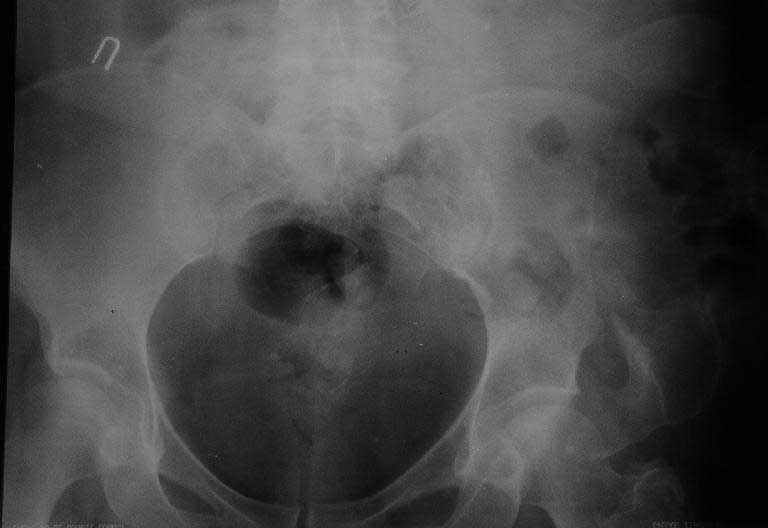

Грыжа сквозь крыло таза

Женщина 51 г. полтора года назад попала в автоаварию, был перелом таза и голени, лечилась консервативно, на вытяжении недель 6, потомх одила с костылями.

Через 3 мес. после травмы обратила внимание на выпячивание сбоку таза. Картина на сегодня на рентгенограммах и фото. Похоже, это грыжа сквозь несросшееся крыло подвздошной кости. Как тут правильно сформулировать диагноз? Что лучше предпринять для ликвидации грыжи?